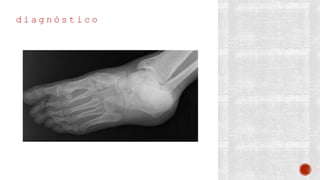

d i a g n ó s t i c o

¬ Clínico

¬ Radiológico

- AP de tobillo

- Lateral de tobillo

- De mortaja

- AP de pie

- Lateral de pie

- Oblicua de pie

- Proyección de Canale

- TAC

- Gammagrafía ósea con tecnecio 99

- RM